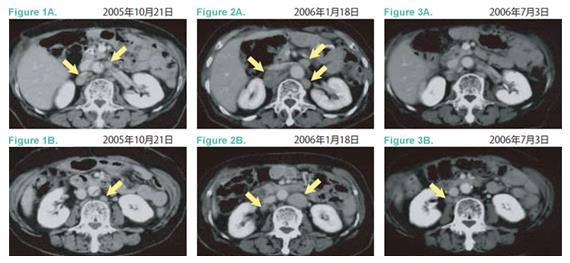

- 2005年10月肿瘤标志物再上升,腹部CT显示旁大动脉淋巴结复发(Figure1A、B)。化疗副作用腹泻、强烈恶心,体重明显先将,随机中止TS-1,进入维持性支持治疗。2005年11月开始服用中草药。2006年1月18日发现新的淋巴结转移,及原病灶增大(Figure2A、B),左锁骨上淋巴结转移。

- 2006年3月24日开始询问免疫细胞治疗,PS0,左锁骨上淋巴结肿大可触。4月7日开始体淋巴活化治疗(CD3-LAK),每2周1次。截至6月20日共治疗6次。患者本人定期往福岛县温泉疗养。此间CA19-9指标在下降,左锁骨上淋巴结缩小,触诊已经摸不到。7月3日CT影像显示旁大动脉淋巴结缓解(Figure3A、B)。之后该患者每6周接受一次免疫细胞治疗,患者全身状态良好,食欲佳。